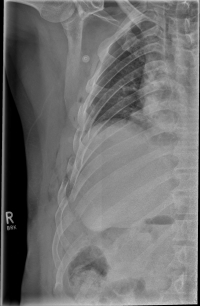

Rib Fractures

The rib fracture is a common injury to the chest. It occurs frequently in (car) accidents, falls during cycling and contact sports. Due to their anatomical position, especially the 4th - 9th ribs are affected.

If three or more ribs are broken on the same side, this is called a flail chest. A rib fractured in more than one place is called a piece break.

As a rule, the rib fracture is diagnosed by X-ray. In severe cases or ambiguous X-ray findings, a layer imaging, for example computer tomography (CT), can also be performed.